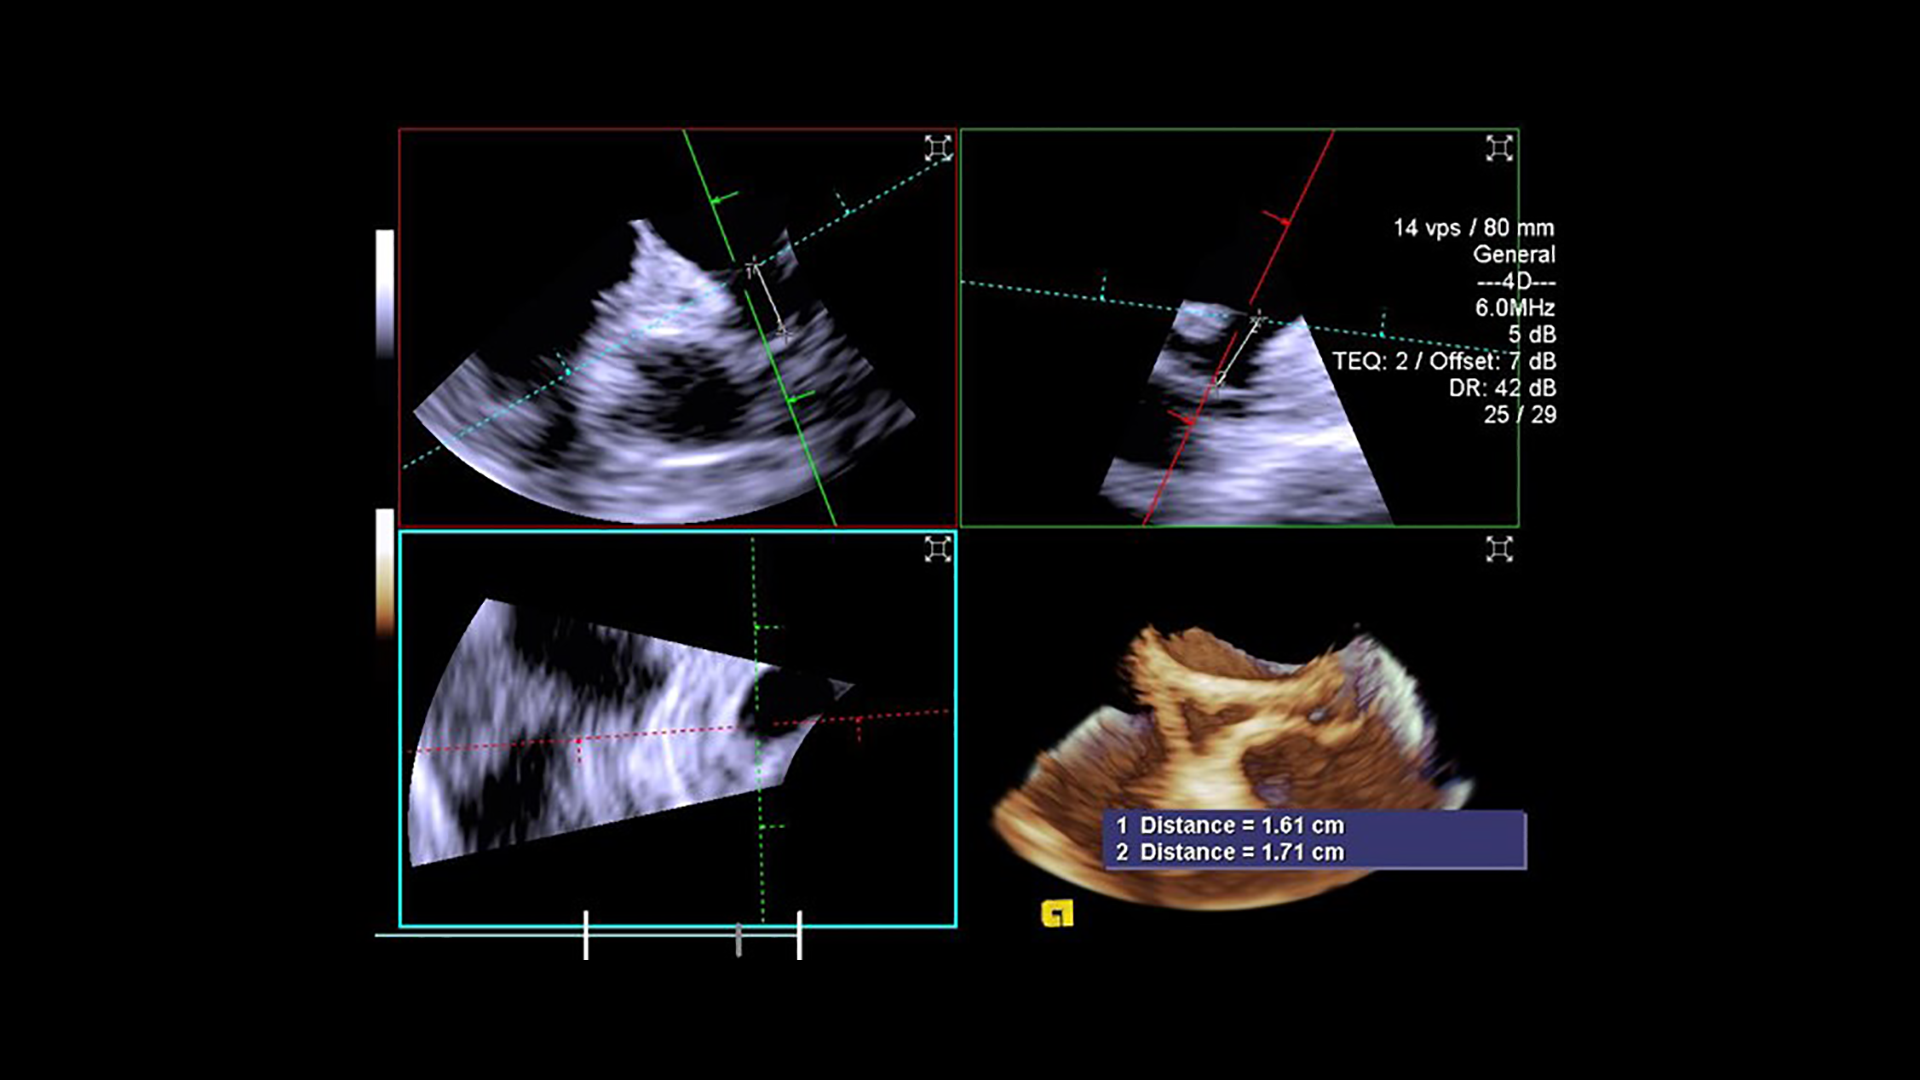

Ice Catheter Siemens .  introducing the acunav lumos 4d ice catheter, delivering incredible image quality and precise procedural guidance. In matters of the heart, visualization matters. Learn more about our newest.   the acunav volume ice catheter transforms care delivery by enabling treatment of patients who were.  with the acuson acunav volume 4d ice catheter, you can take on the most complex cases with the highest standard in.   acuson acunav volume ice catheter.   siemens healthineers has received ce mark for the acunav volume ice (intracardiac echocardiography) catheter, which is a. See full details of the heart in dynamic 4d motion even while imaging patients in.  * the acuson acunav 4d ice catheter enables precise orthogonal plane measurements with reference planes.  acuson acunav volume ice catheter. This is command, in your hands.   according to siemens, the acunav volume ice catheter enables treatment of patients who were previously.

with the acuson acunav volume 4d ice catheter, you can take on the most complex cases with the highest standard in.   siemens healthineers has received ce mark for the acunav volume ice (intracardiac echocardiography) catheter, which is a. See full details of the heart in dynamic 4d motion even while imaging patients in.  introducing the acunav lumos 4d ice catheter, delivering incredible image quality and precise procedural guidance.  acuson acunav volume ice catheter.  * the acuson acunav 4d ice catheter enables precise orthogonal plane measurements with reference planes.   according to siemens, the acunav volume ice catheter enables treatment of patients who were previously.   the acunav volume ice catheter transforms care delivery by enabling treatment of patients who were. Learn more about our newest.   acuson acunav volume ice catheter.

Ice Catheter Siemens  In matters of the heart, visualization matters. In matters of the heart, visualization matters.   acuson acunav volume ice catheter. Learn more about our newest.  introducing the acunav lumos 4d ice catheter, delivering incredible image quality and precise procedural guidance.  with the acuson acunav volume 4d ice catheter, you can take on the most complex cases with the highest standard in.   siemens healthineers has received ce mark for the acunav volume ice (intracardiac echocardiography) catheter, which is a.  acuson acunav volume ice catheter.  * the acuson acunav 4d ice catheter enables precise orthogonal plane measurements with reference planes.   according to siemens, the acunav volume ice catheter enables treatment of patients who were previously.   the acunav volume ice catheter transforms care delivery by enabling treatment of patients who were. This is command, in your hands. See full details of the heart in dynamic 4d motion even while imaging patients in.

ACUSON AcuNav Volume 4D ICE Catheter Siemens Healthineers USA Ice Catheter Siemens   * the acuson acunav 4d ice catheter enables precise orthogonal plane measurements with reference planes.  introducing the acunav lumos 4d ice catheter, delivering incredible image quality and precise procedural guidance. See full details of the heart in dynamic 4d motion even while imaging patients in. In matters of the heart, visualization matters.   the acunav volume ice catheter. Ice Catheter Siemens.